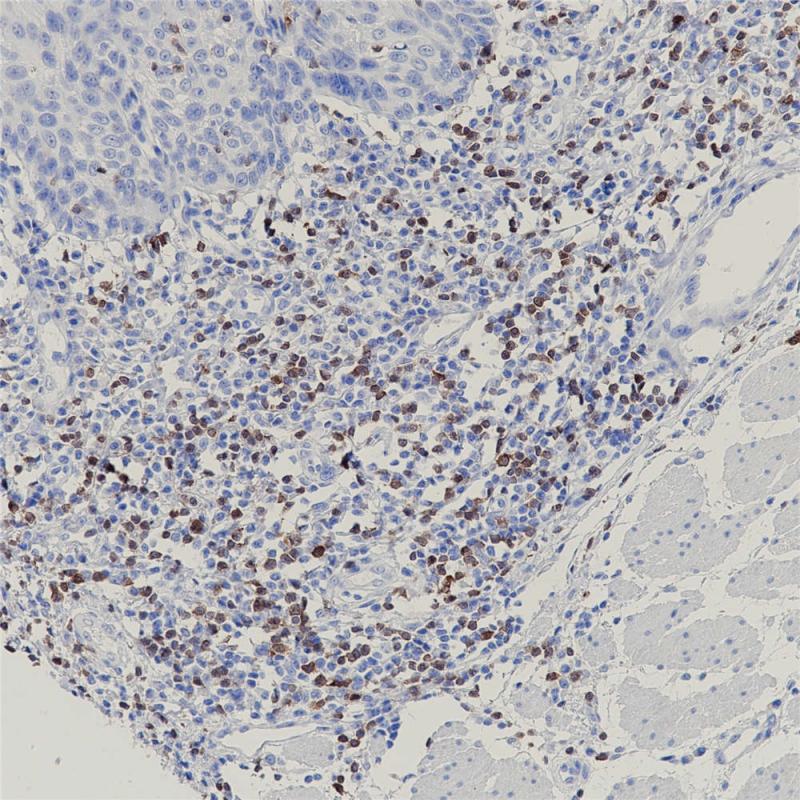

ZAP-70 重组兔单克隆抗体

ZAP-70是Syk家族的一种酪氨酸激酶,主要表达于T细胞、NK细胞、肥大细胞和嗜碱性粒细胞。在正常前体B细胞也可以检测到,但是在正常成熟B细胞中不表达。 ZAP-70与慢性淋巴细胞白血病的免疫球蛋白重链可变区基因(IgVH)的非突变结构形成密切相关。该抗体可作为慢性淋巴细胞白血病的一种独立预后指标,对其临床指导治疗具有重要意义。

阳性对照

扁桃体

亚细胞定位

细胞核/细胞质